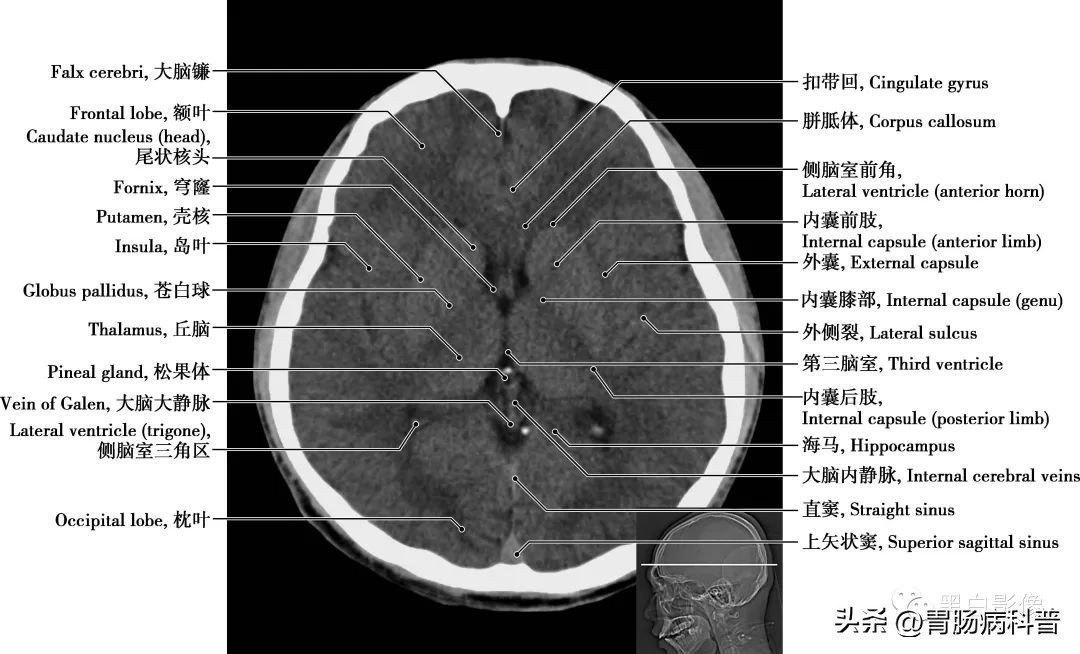

图1-1-10 经第三脑室轴位切面

第三脑室 位于间脑中央,为两侧丘脑和下丘脑之间的矢状窄隙,前方借室间孔与侧脑室相通,后方与第四脑室相通。丘脑 为间脑最大的卵圆形灰质核团,位于第三脑室两侧,左、右丘脑借灰质团块相连,其被“丫”形白质板分成前、内侧和外侧三大核群。受损时,对侧偏身感觉减退,对侧动作性震颤或偏身共济失调伴舞蹈徐动症,情绪不稳等